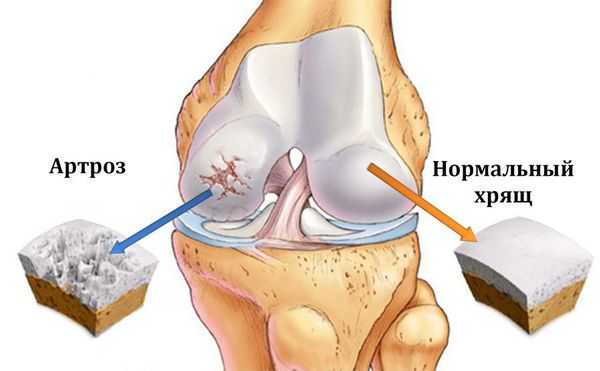

При артрозе (остеоартрозе) кроме прогрессивного разрушения хряща, потери его эластичности и амортизирующих свойств, в процесс постепенно вовлекаются кости. [7] [29] Под нагрузкой возникают заострения по краям (экзостозы), которые по ошибке считают "отложениями солей" — при классическом артрозе никакого отложения солей не происходит. Прогрессируя, артроз продолжает «съедать» хрящ. Затем деформируется кость, там происходит образование кист, поражаются все структуры сустава, и нога искривляется. [11] [17]

Деформирующий остеоартроз - частая патология суставов, при которой нарушение регенерации соединительнотканных структур приводит к преждевременному старению суставного хряща - его истончению, шероховатости, растрескиванию, потере прочности и эластичности. Субхондральная кость обнажается и уплотняется, в ней происходят остеосклеротические изменения, образуются кисты и краевые разрастания - остеофиты.

Патогенез остеоартроза